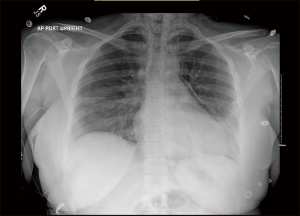

No other complications were identified post-operatively (Figure 7). The patient’s radiculopathy and myelopathy resolved with resolution of the neck pain, and she has returned to work as a case manager.

Figure 7 Three months post-operative radiograph. MKL, mild kyphotic loss of cervical lordosis.